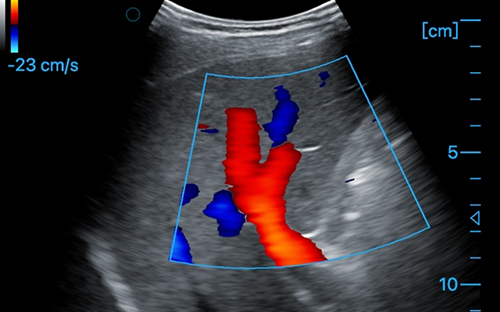

Liver + CF

Liver + CF